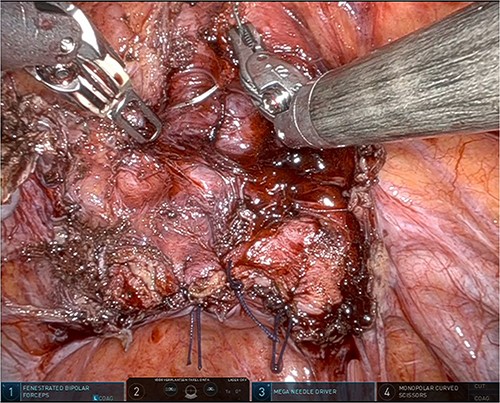

The patient was planned for a robotic resection of the endometriosis nodule and hysterectomy by an experienced robotic gynecological surgeon. The patient was placed on a PinkPad (Kebomed Europe AG) in a lithotomy position. Cystoscopy was performed with placement of ureteral stents. Double-J stents were guided up to the kidneys. Instillation of 200 ml physiologic water with 2 cc of ICG (1.9 mg/cc) in an empty bladder, with subsequent clamping of the urinary catheter (Fig. 3). The da Vinci Xi robot platform (Intuitive Surgical Inc.) was used. Instruments used were: bipolar fenestrated forceps, unipolar scissor, Cadière forceps, and Vessel Sealer Extend. Circumferential incision, dissection and detachment of the endometriotic nodule from the posterior bladder wall was performed under guidance of NIR imaging and ICG, whilst the endometriosis nodule remained stuck on the uterine isthmus (Fig. 4; Supplementary Video). During the dissection, perforation of the bladder mucosa could be avoided, with transparency of the bladder mucosa by ICG. During the hysterectomy part, the bladder catheter was unclamped. The posterior bladder wall was repaired longitudinally. The muscular layers and serosa of the bladder were sutured with Monocryl 3/0 in a two-layer closure (Fig. 5). The bladder was filled with 200 cc of physiologic water with ICG, no bladder leakage nor clear transparency by ICG of the posterior bladder wall was seen. The total operative time was 120 min. The total blood loss was 25 mL. There were no perioperative complications. The length of the hospitalization was 48 hrs. Oxybutynin was given to prevent bladder spasms from the urinary catheter and/or stents. The Foley catheter was removed after 9 days, and the ureteral stents removed after 10 days. At the 2-week outpatient visit the patient was satisfied, and didn’t experience any pain nor urinary voiding problems.

Suturing the posterior bladder wall in a two-layer closure, first the submucosa and muscular layer and second the muscular layer and serosa.